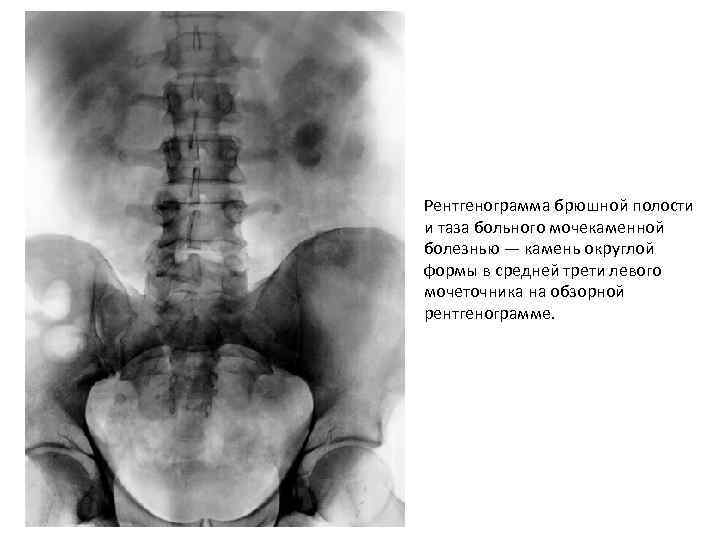

Рентгенограмма брюшной полости и таза больного мочекаменной болезнью — камень округлой формы в средней трети левого мочеточника на обзорной рентгенограмме.